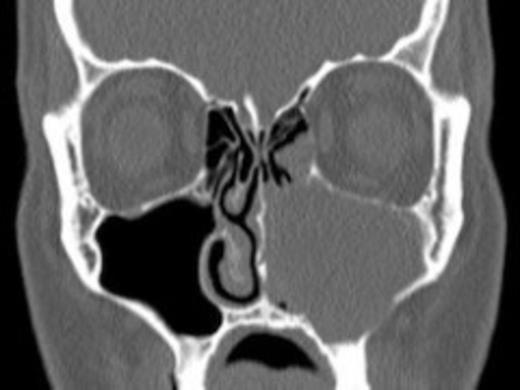

Axial computed tomography scans with coronal reformats were acquired through the paranasal sinuses. This demonstrated obstruction of the left nasal airway. There was complete opacification of the left maxillary sinus with obscuration of the osteomeatal complex. Expansion and thinning of the medial wall of the maxillary antrum was also noted. The remaining paranasal sinuses were clear. The postnasal spaces were equal and symmetrical and there was no evidence of focal bony destruction.